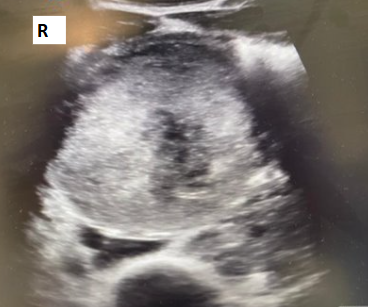

Historia clínica: Antecedentes personales: no enfermedades previas de interés, no antecedentes quirúrgicos, no alergias conocidas. Hábitos tóxicos: tabaco 1 paquete/día; cocaína, cannabis y TUSI, uso recreativo; alcohol, ocasional. Anamnesis: Paciente masculino de 28 años de aspecto atlético, que consulta por dolor abdominal de inicio súbito en epigastrio y mesogastrio, EVA 8/10, de 4-5 horas de evolución, sin otros síntomas asociados. Refiere consumo de anabolizantes (anabolizantes del GYM: boldenona, testosterona), además de proteína y creatina. Exploración: TA: 155/100 Abdomen: RHA presentes y conservados, abdomen blando, depresible, doloroso a la palpación superficial ni profunda en mesogastrio e hipogastrio. Sin signos de irritación peritoneal. Pruebas complementarias: Ecografía A pie de cama Se realiza barrido con sonda convexa; se observan dos masas lobuladas en la región del mesogastrio, heterogéneas e hiperecogénicas, derecha con área anecoica, diámetro aproximado de 16 cm, con paredes bien definidas, que no capta con Doppler. Tras control del dolor, se decide remisión al hospital de referencia, donde se completa estudio con analíticas, TAC y BAG de las lesiones: Analíticas: LDH 1,361 U/L (<300), PROTEÍNA C REACTIVA 17,19 mg/dL (<0,5), BETA-2 MICROGLOBULINA 2.903 µg/L (<2,5). BETA HCGMT 5,43 mU/mL (<5). TAC: CONCLUSIÓN: Las lesiones descritas presentan aspecto inespecífico, debiendo plantear dentro de diferentes posibilidades diagnósticas que correspondan a extensos conglomerados ganglionares o lesiones infiltrativas primarias/secundarias, incluso debiendo plantear como posibilidad tumores germinales. BAG de las lesiones eco guiada: Anatomía patológica SEMINOMA